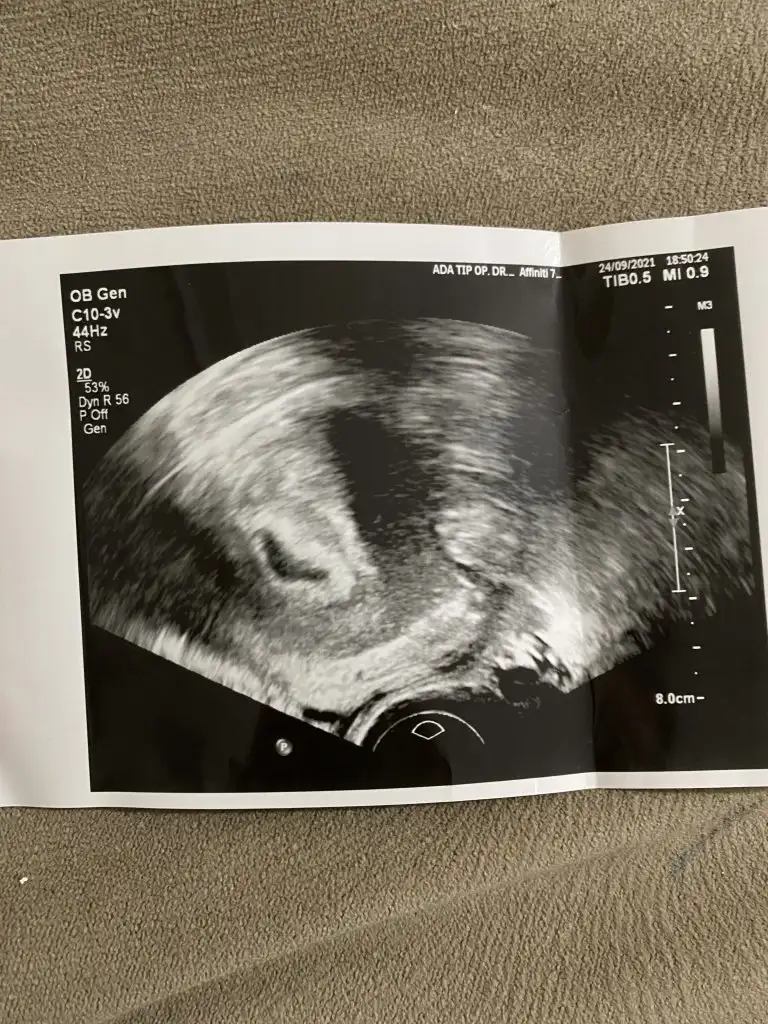

Selamlar herkese 5+5 haftalık bebişim. vajinal bakıldı.sizce kızmı erkek mi

Banada tahminde bulunabilecek biri var mı vaginal usg

Ramzi teorisine göre ( bilimsel bir araştırma sonucuymuş ve %85 doğruluğu varmış). İlk 6-8 haftalık ultrason görüntüsüne göre bebeğin kesenin içersinde soldan ya da sağdan girişine göre cinsiyet tahmini yapılıyor. Bilimsel olunca tecrübeli annelerimiz yada anne adaylarımızdan yardım istiyoruz. Doğruluğu var mı öğrenmek adına :) Bizleri aydınlatırsanız çok seviniriz. bu teorieye göre;

Vajinal muayeneyle bakıldıysa eğer;

Sağdan girmiş gözüküyosa aslında solmuş ve ERKEK,

Soldan girmiş gözüküyosa aslında sağmış ve KIZ ,

Karından bakıldıysa eğer,

Soldan girmiş gözüküyosa gerçektede solmuş ve ERKEK,

Sağdan girmiş gözüküyosa gerçekte de sağmış ve KIZ,

Bi teori anca bu kadar yanliş anlatilabilirdi ..arkadaşlar ramzi teorisini araştiran biri bunun doğru olmadiğini anlar ..doğru yorum yapabilmek için bebeğin konumuna gore değil plesantanin konumuna göre yorum yapılmasi gerekiyordu